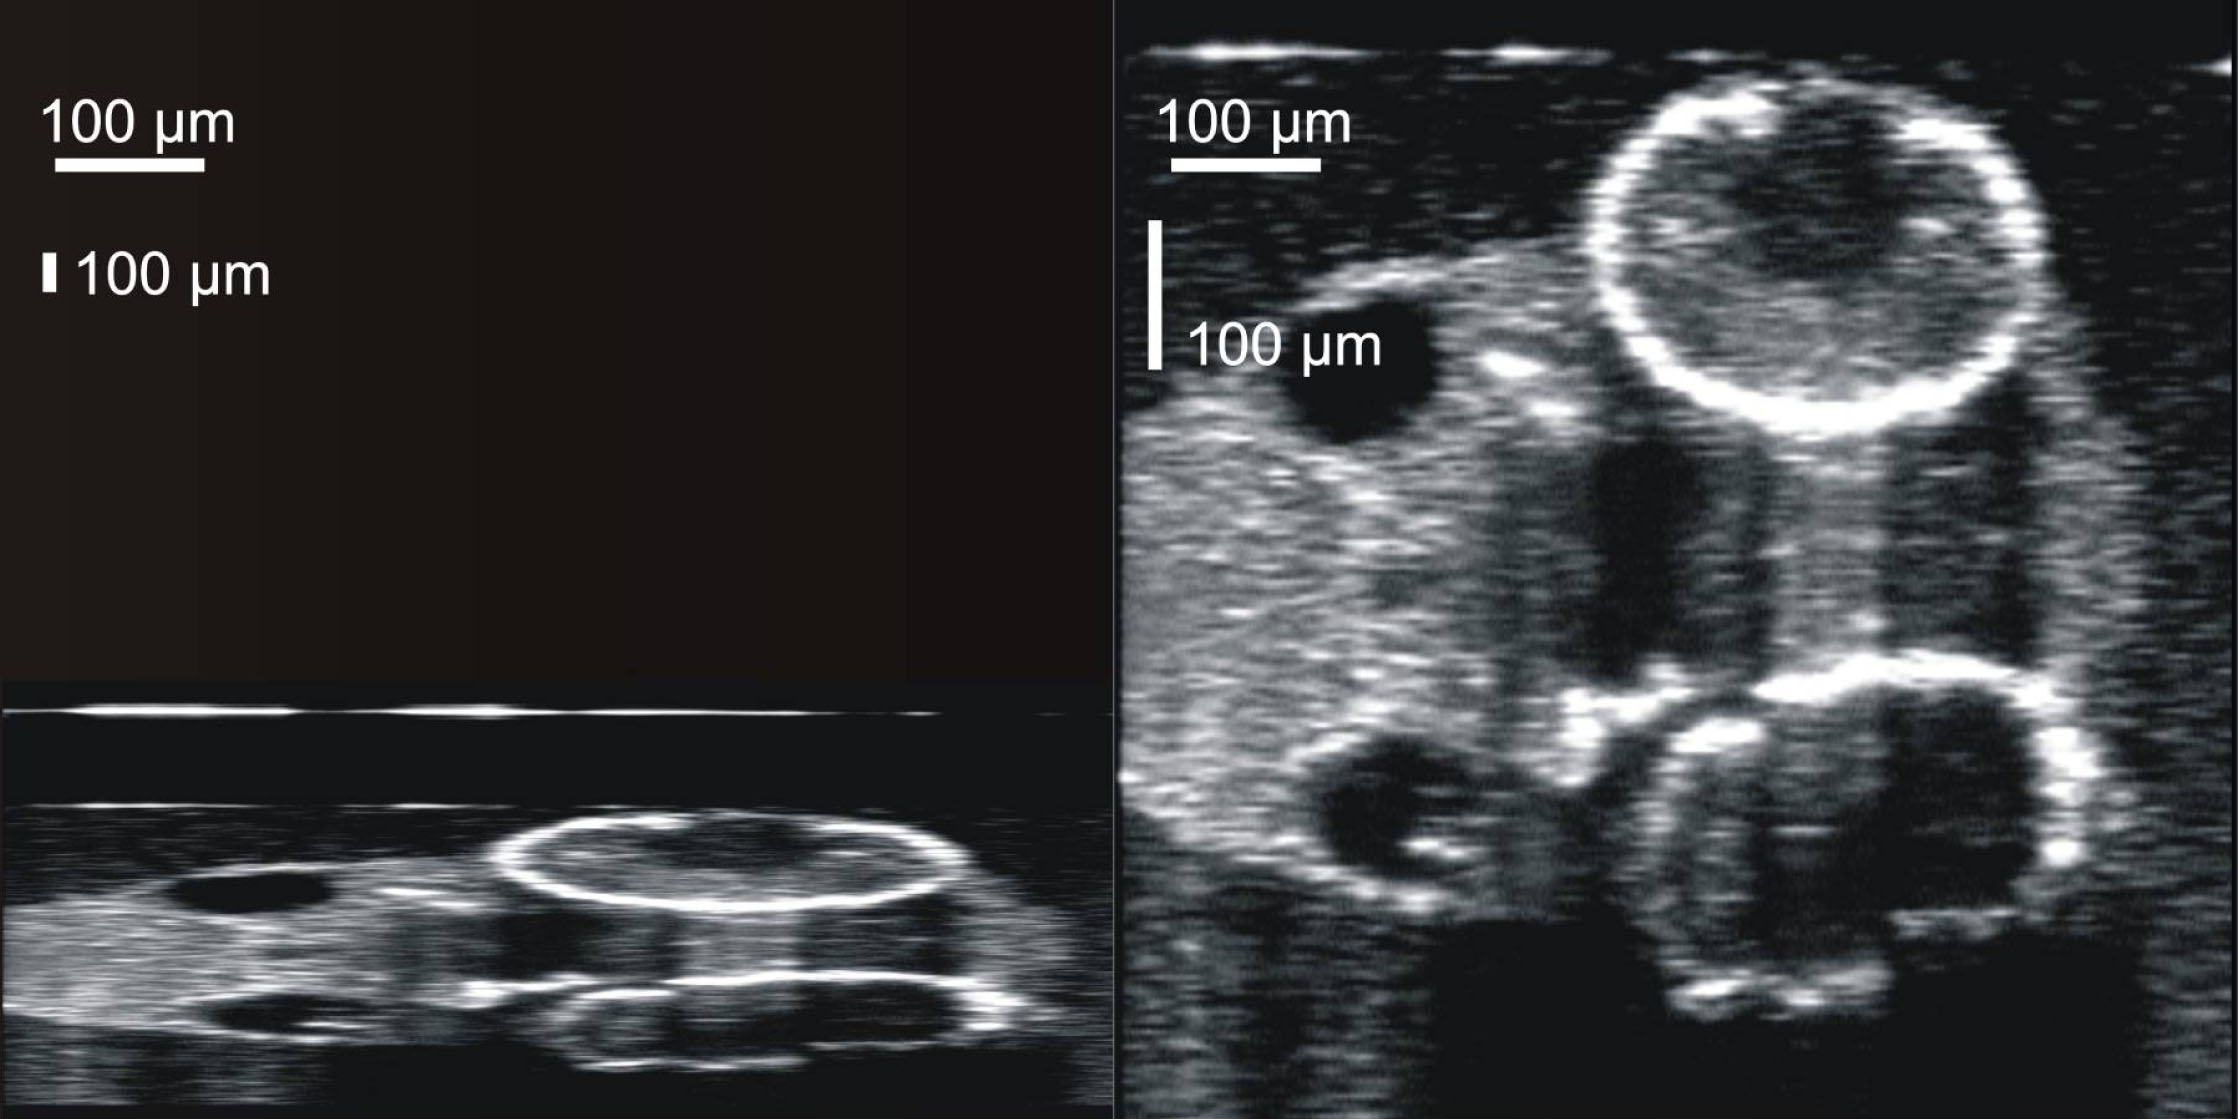

Figure 4. Images were resampled to correct

the irregular data density of the raw scans. The Z axis (vertical axis

of the image) is fixed at 1,024 reflectance measurements along a 2 mm

line. A X,Y scanning pattern was optimized for the body of the animal,

with a X,Y a-scan density of 501x180, yielding the uncorrected aspect

ratio observed in the left frame. Scan data were resampled, utilizing

spline interpolation, to produce images with a 1:1 aspect ratio for

structural measurements and visualization.